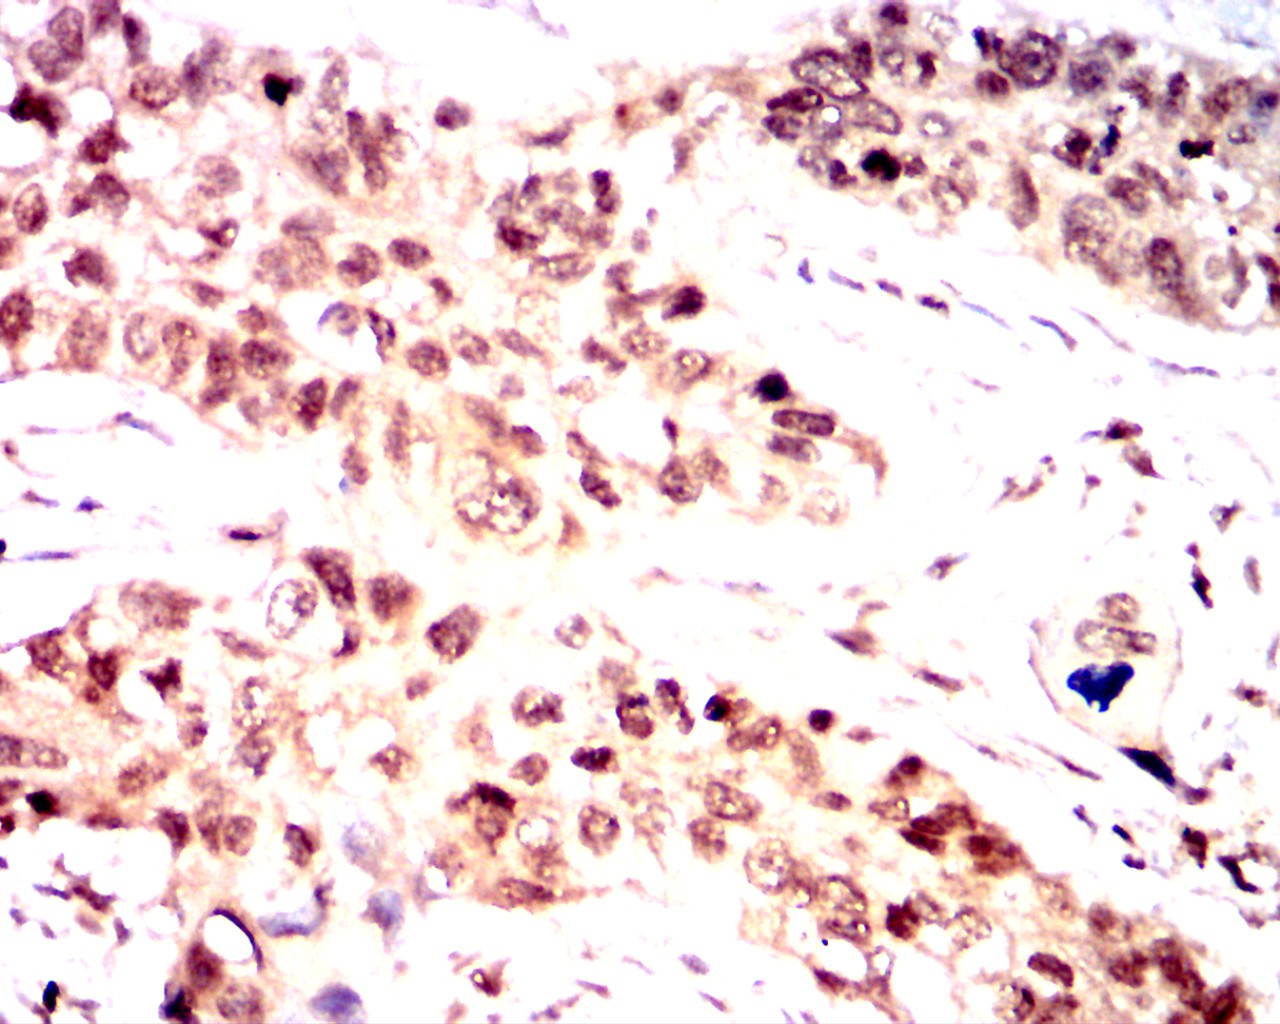

Immunohistochemical analysis of paraffin-embedded colon cancer tissues using Nanog antibody with DAB staining.Pre-treat the sections with heat-mediated antigen retrieval using sodium citrate buffer (pH 6.0) (OM750020) for 2 minutes. Wash the sections with ddH₂O and PBS (OM750003). Block the tissue with 10% non-immune goat serum(OM760028) at room temperature for 30 minutes. Incubate the tissue with the primary antibody diluted at a ratio of 1:1500 at 4°C overnight. At room temperature, dilute the secondary antibody, Goat Anti-Mouse IgG (H&L) - HRP(OM644366), at a ratio of 1:200 and incubate for one hour. Use DAB(OM760029)as the chromogenic agent. Counterstain the tissue with hematoxylin, and mount the tissue sections with neutral gum.IHC

Immunohistochemical analysis of paraffin-embedded colon cancer tissues using Nanog antibody with DAB staining.Pre-treat the sections with heat-mediated antigen retrieval using sodium citrate buffer (pH 6.0) (OM750020) for 2 minutes. Wash the sections with ddH₂O and PBS (OM750003). Block the tissue with 10% non-immune goat serum(OM760028) at room temperature for 30 minutes. Incubate the tissue with the primary antibody diluted at a ratio of 1:1500 at 4°C overnight. At room temperature, dilute the secondary antibody, Goat Anti-Mouse IgG (H&L) - HRP(OM644366), at a ratio of 1:200 and incubate for one hour. Use DAB(OM760029)as the chromogenic agent. Counterstain the tissue with hematoxylin, and mount the tissue sections with neutral gum.